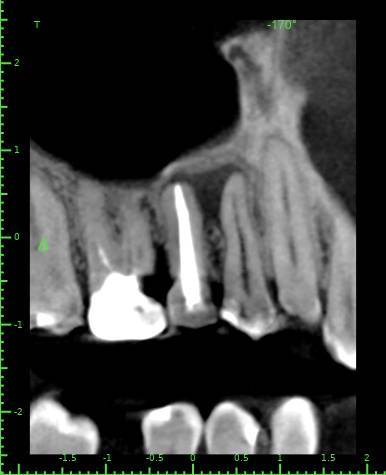

Здравствуйте, появился полгода назад свищ на десне, заполняется и лопается, затягивается и снова появляется, спустя пару месяцев обратился в стоматологию, на снимке ничего критичного не увидели, отправили домой наблюдать тип, еще прошло 3 месяца, так и не проходит и хуже не стало, болей нет никаких, только небольшая если трогать в районе свища, пойдя в другую стоматологию, сделали снимок и так же непонятно что и почему, пошел на КТ, и обратно в стоматологию, есть какая то полость, можно попробовать но нет гарантии, что пройдет, прикрепляю снимок К

ТРезультаты и плюс программа для открытия